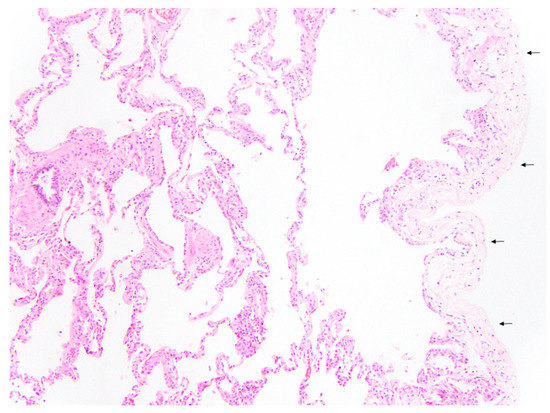

- Kovach, A.E.; Magcalas, P.M.; Ireland, C.; McEnany, K.; Oliveira, A.M.; Kieran, M.W.; Baird, C.W.; Jenkins, K.; Vargas, S.O. Paucicellular fibrointimal proliferation characterizes pediatric pulmonary vein stenosis: Clinicopathologic analysis of 213 samples from 97 patients. Am. J. Surg. Pathol. 2017, 41, 1198–1204. [Google Scholar] [CrossRef]

- Pogoriler, J.E.; Kulik, T.J.; Casey, A.M.; Baird, C.W.; Mullen, M.P.; Jenkins, K.J.; Vargas, S.O. Lung Pathology in Pediatric Pulmonary Vein Stenosis. Pediatr. Dev. Pathol. 2016, 19, 219–229. [Google Scholar] [CrossRef]